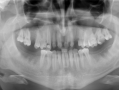

Rozległa torbiel zawiązkowa żuchwy

Paulina Adamska, Maria Mikołajska, Anna Janowska, Anna Starzyńska